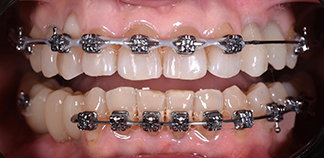

До лечения

Жалобы на скученность зубов.

Как лечили

Ортодонтическое лечение на брекетах. Проведена имплантация и установлены временные коронки в дальнейшем будут установлены постоянные.

Лечащие врачи

СЕМИВОЛОВА Анастасия Владимировна, МИРОШНИЧЕНКО Алексей Михайлович, БАЛЕВ Дмитрий Олегович